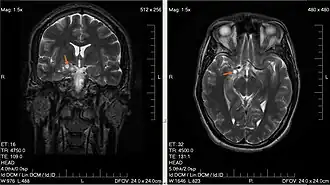

Description de cette image, également commentée ci-après

Gliome chez un homme de 28 ans (flèche orange).